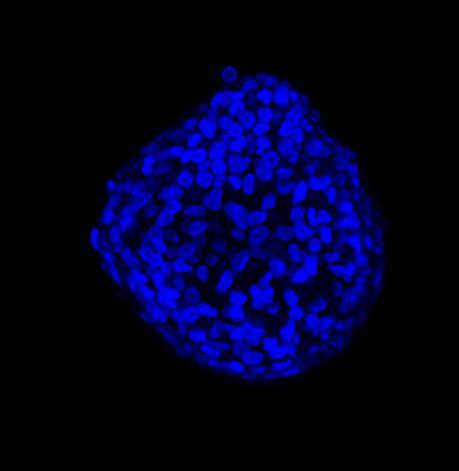

为了更好地理解 3D 细胞组织,在图 C 中,我们展示了使用两种物镜获得的同一球体的体积视图(120 um 厚),甚至在 3D 肿瘤球体的更深区域也能看到染色。最后,在 图 D 中,显示了使用 25 倍硅油物镜获得的整个球体的 3D 电影特效。

图 D:使用 25 倍硅油物镜获得的 3D 球体的 3D 电影特效。活细胞用钙黄绿素(绿色)标记,死细胞用 PI(红色)标记。细胞核用 Hoechst(蓝色)染色。150 um 厚。此图像是使用 CrestOptics X-Light V3 转盘获取的。